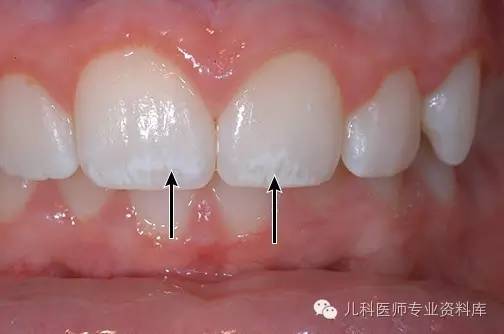

所谓氟斑牙就是因为摄入氟过多,导致牙釉质上的钙流失超过沉积,从而导致牙齿表面出现白色或黄色的斑点或带状斑纹,严重者出现褐色斑、缺损。见下图:

上图是轻度的氟斑牙:箭头处。

02.钙化的完全,那牙釉质就是半透明的,能显示出牙本质的颜色,微黄色;如果钙化不完全,就是不透明的白色,看着很洁白,如第一幅图中氟斑牙的颜色。